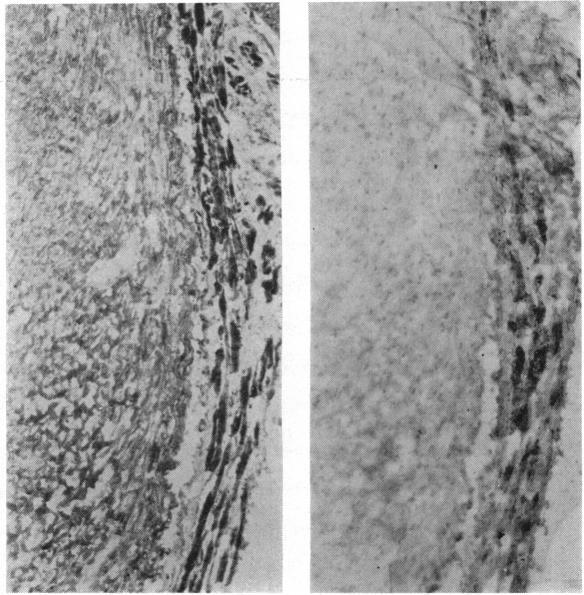

LOCALIZATION OF MONOAMINE OXIDASE IN MAMMALIAN AND REPTILIAN HEART.

Br Heart J. 1965 Jan;27(1):116-20. doi: 10.1136/hrt.27.1.116.